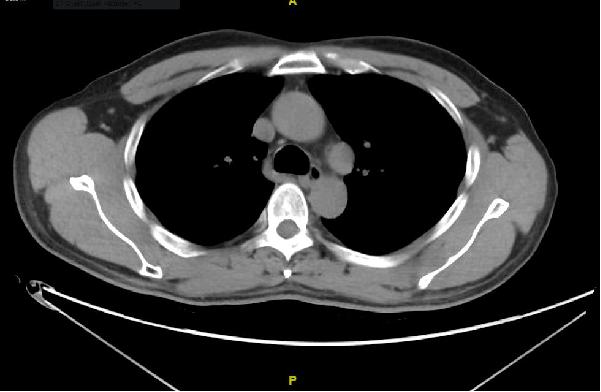

2016年5月第二次介入治疗:TAE+射频消融

碘油标记

排查病灶

COOLTIP 160W/16min